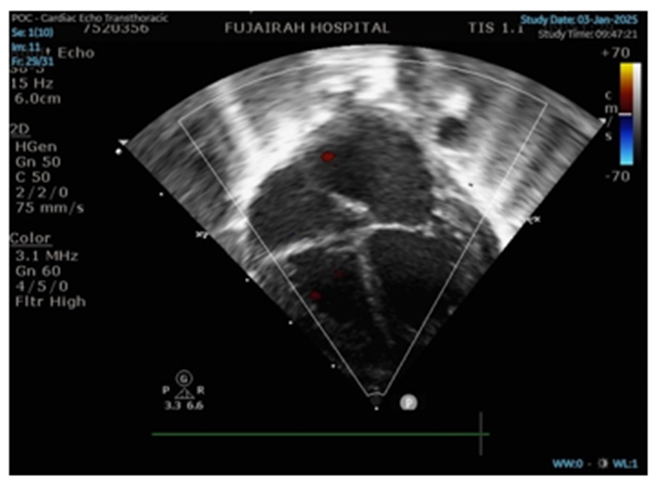

Echocardiography demonstrated progressive dilation of the left atrium and left ventricle with preserved systolic function, suggestive of early dilated cardiomyopathy (Figure 2). The aortic valve was functionally bicuspid (Figure 3). Frequent premature atrial and ventricular contractions were observed, likely secondary to metabolic instability. Medical management included captopril, spironolactone, and hydrochlorothiazide.

Figure 2: Apical 4 chambers view reveals LA and LV dilation.

Cardiac involvement, including early dilated cardiomyopathy and arrhythmias, is well-documented in mitochondrial disorders and has been reported in over 50% of COQ10D5 cases [9]. Our patient developed progressive atrial and ventricular dilation with preserved systolic function, managed conservatively. Though cardiac manifestations may sometimes respond to CoQ10, the progressive nature in this case underscores the aggressive disease phenotype.